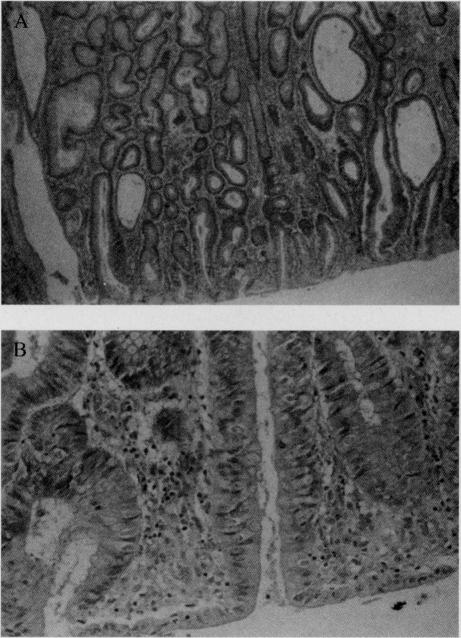

家族性腺瘤性息肉病:一例病例报告及文献综述

Familial adenomatous polyposis (FAP) is an autosomal dominant condition characterized by diffuse intestinal polyposis, specific gene mutation, and predisposition for developing colon cancer. Left untreated, patients with FAP will develop colorectal carcinoma during early adulthood. Hence, early detection and surgical intervention are of the utmost importance. Colectomy is required and may include an ileal pouch with ileoanal anastomosis, which eliminates the colon and rectal disease while preserving fecal continence and avoidance of a permanent ileostomy. Advances in the treatment of FAP with associated reduction in mortality from colorectal carcinoma make extracolonic manifestations of the disease more common and life-long surveillance is mandatory. The most life-threatening extracolonic manifestations of FAP are periampullary carcinoma and desmoid tumors. The upper gastrointestinal tract should be monitored endoscopically at the time of diagnosis and assessed regularly thereafter. Duodenal adenomas should be resected so as to avoid the devastating effects of invasive periampullary carcinoma. Additionally, the development of desmoid tumors needs to be monitored (by CT or MRI), so as to avoid the severe complications of local invasion. Further research is indicated in the development of effective screening and treatment for this condition.

家族性腺瘤性息肉病(FAP)是一种常染色体显性遗传病,其特征为弥漫性肠道息肉、特定基因突变以及患结肠癌的倾向。若不治疗,FAP患者在成年早期会发展为结直肠癌。因此,早期检测和手术干预至关重要。需要进行结肠切除术,可能包括回肠储袋肛管吻合术,该手术可消除结肠和直肠疾病,同时保持大便失禁并避免永久性回肠造口术。FAP治疗的进展以及结直肠癌死亡率的相应降低,使得该疾病的结肠外表现更为常见,因此终身监测必不可少。FAP最危及生命的结肠外表现是壶腹周围癌和硬纤维瘤。在诊断时应通过内镜监测上消化道,并在此后定期评估。十二指肠腺瘤应予以切除,以避免侵袭性壶腹周围癌带来的毁灭性影响。此外,需要监测硬纤维瘤的发展(通过CT或MRI),以避免局部侵袭的严重并发症。对于这种疾病,在有效筛查和治疗的发展方面还需要进一步研究。